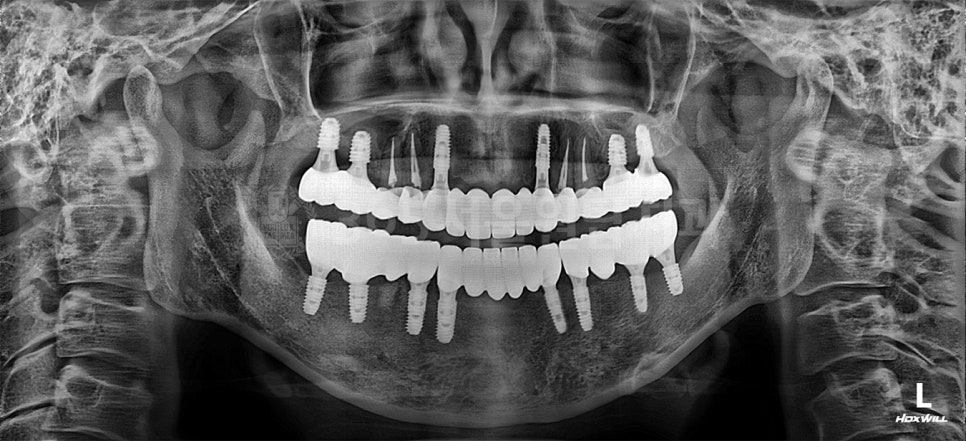

임플란트는 심는 것으로 끝나지 않습니다.

그 위에 올라갈 치아(보철)까지 고려해야

비로소 치료가 완성됩니다.

CT를 통해

• 임플란트가 들어갈 각도

• 씹는 힘이 전달되는 방향

• 주변 치아와의 관계

를 함께 확인합니다.

방향이 조금만 어긋나도

나중에 씹는 불편감이나

임플란트에 과도한 힘이

실릴 수 있습니다.

그래서 저는

수술보다 ‘계획’에

더 많은 시간을 쓰는 편입니다.

임플란트는 수술 전에 치료 계획으로 이미 절반이 결정됩니다.

화곡동임플란트 성공은 올바른 치료 계획에서 시작됩니다.